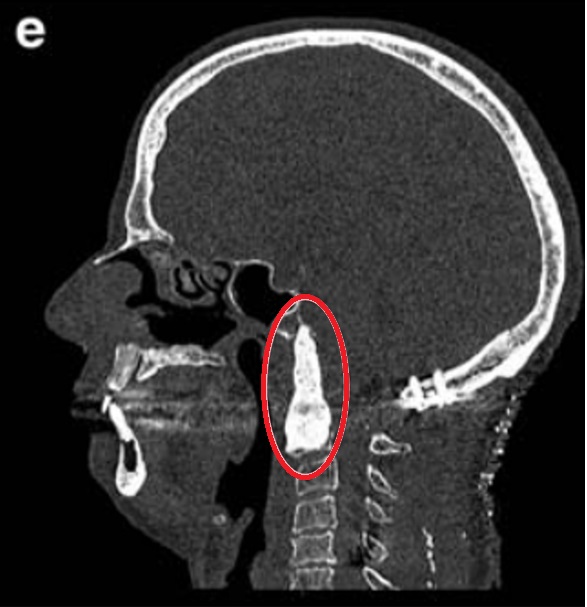

2019年初随访MRI,显示脊索瘤复发,颅颈交界区脊索瘤病变大小为51.3×74.3×25.9 mm,脊索瘤已经引起C2椎体病理性骨折及C1水平脊髓压迫,伴随C1右侧方、C1前后弓、C2椎体侵犯,齿状突后移和C1水平的侧向移位(图6)。肿瘤侵袭上三分之一的髁突和斜坡水平(图6a-c)。肿瘤侵袭延伸至C5-C6水平,在椎前间隙浸润延伸,并压迫C5和C6神经根,并包裹椎动脉椎动脉的V2段(图6d)。临床检查显示神经反射亢进和Lhermite征阳性。

▼图a-b术前MR显示颅颈交界区较大脊索瘤,51.3×74.3×25.9 mm大小,浸润性生长。

▼图显示脊索瘤向周边浸润生长,下至C5-C6水平的脊髓瘤侵犯浸润。